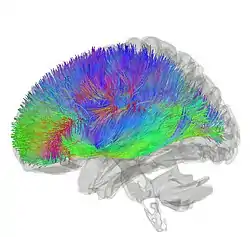

![]() Tractography showing corticostriatal connections | |

Inputs

[30] The largest connection is from the cortex, in terms of cell axons. Many parts of the neocortex innervate the dorsal striatum. The cortical pyramidal neurons projecting to the striatum are located in layers II-VI, with the most dense projections come from layer V.[31] They end mainly on the dendritic spines of the spiny neurons. They are glutamatergic, exciting striatal neurons.

The striatum is seen as having its own internal microcircuitry.[32] The ventral striatum receives direct input from multiple regions in the cerebral cortex and limbic structures such as the amygdala, thalamus, and hippocampus, as well as the entorhinal cortex and the inferior temporal gyrus.[33] Its primary input is to the basal ganglia system. Additionally, the mesolimbic pathway projects from the ventral tegmental area to the nucleus accumbens of the ventral striatum.[34]

Another well-known afferent is the nigrostriatal connection arising from the neurons of the substantia nigra pars compacta. While cortical axons synapse mainly on spine heads of spiny neurons, nigral axons synapse mainly on spine shafts. In primates, the thalamostriatal afferent comes from the central median-parafascicular complex of the thalamus (see primate basal ganglia system). This afferent is glutamatergic. The participation of truly intralaminar neurons is much more limited. The striatum also receives afferents from other elements of the basal ganglia such as the subthalamic nucleus (glutamatergic) or the external globus pallidus (GABAergic).